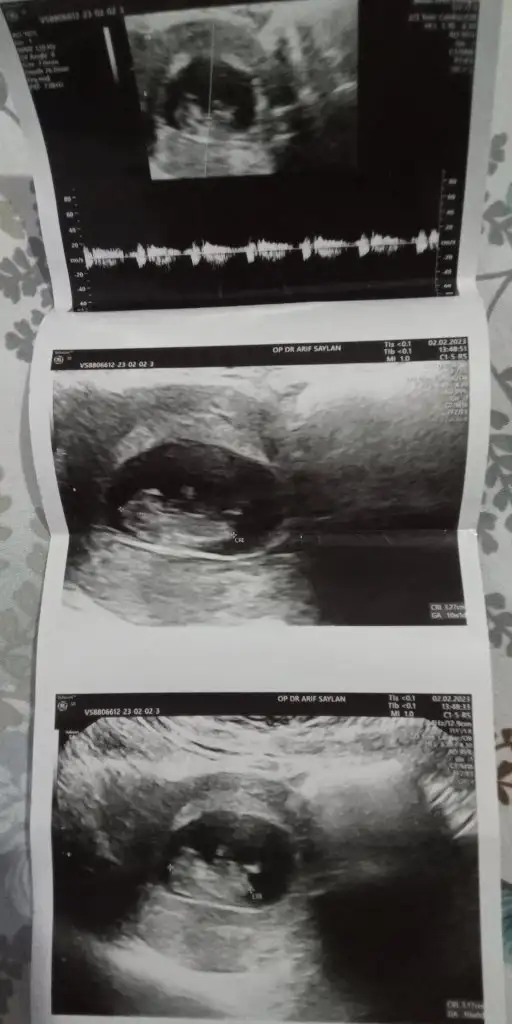

Rica etsem banada bakarmisiniz çok merak ediyorum 🥰☺️❤️

Eklentiler

• Screenshot_20230204-002246.webp

Screenshot_20230204-002246.webp

13,7 KB · Görüntüleme: 92

• IMG_20230202_182730_387.webp

IMG_20230202_182730_387.webp

23,3 KB · Görüntüleme: 67

• IMG_20230202_182706_519.webp

IMG_20230202_182706_519.webp

25 KB · Görüntüleme: 77

• IMG_20230202_182701_639.webp

IMG_20230202_182701_639.webp

27 KB · Görüntüleme: 83